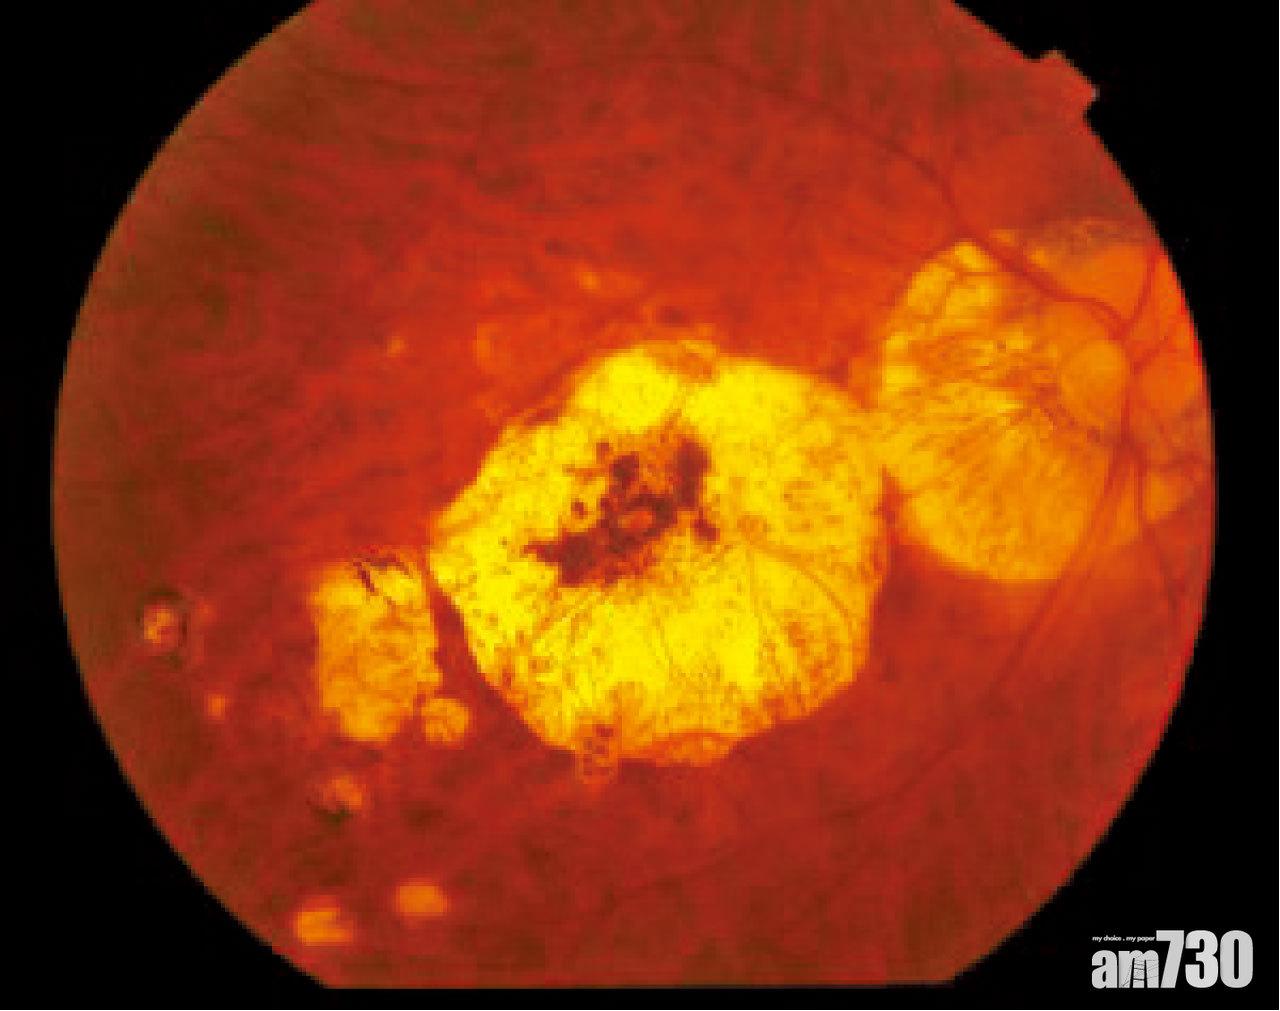

深度近視眼底病變的情況。

深度近視患者的典型眼底特徵為視覺神經頭傾斜、近視弧及豹紋狀眼底,嚴重的更會有漆裂紋、Fuchs疤痕斑和脈絡膜萎縮等。他們的視網膜周邊出現穿孔或撕裂的機會大增,加上眼球中間的玻璃體液化退化收縮,患視網膜脫落的機會便比正常人高15至20倍。常見的病徵為眼前出現黑影或飛蚊、持續性閃光、視野受阻、視力模糊等。

此外,深近視患者的黃斑問題也特別多,包括黃斑裂孔、脈絡膜增生血管、萎縮性視網膜病變等;病徵包括視力減退、影像扭曲、中心視力出現盲點等。由於脈絡膜的增生血管都較脆弱,故容易出血,一旦出現黃斑出血或滲漏情況,視力可於短時間內急劇下降。